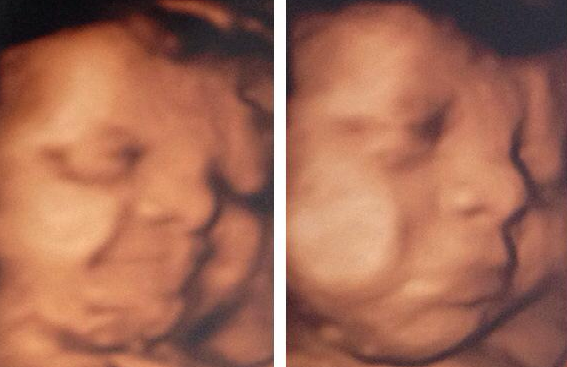

Κατά τη διάρκεια του υπέρηχου ρουτίνας για να μάθουν οι γονείς το φύλο του νέου τους παιδιού όμως, έλαβαν τα σοκαριστικά νέα για το αγοpάκι τους…

Απ” ότι έδειξε η εξέταση, ο γιος της έχει σύνδρομο Down και παρότι για τους άλλους προσπαθούσε να είναι δυνατή και χαμογελαστή, αυτή η μητέρα πέρασε απ” όλα τα στάδια του φόβου, της απογοήτευσης και της απελπισίας. Θα μπορέσεις ο γιος της να είναι ανεξάρτητος;